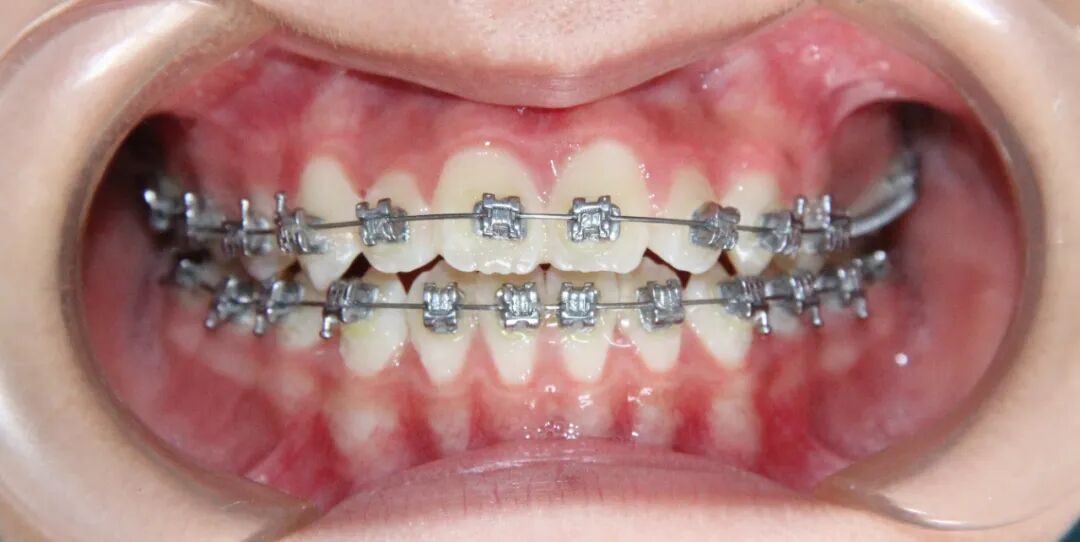

病例1

治疗后